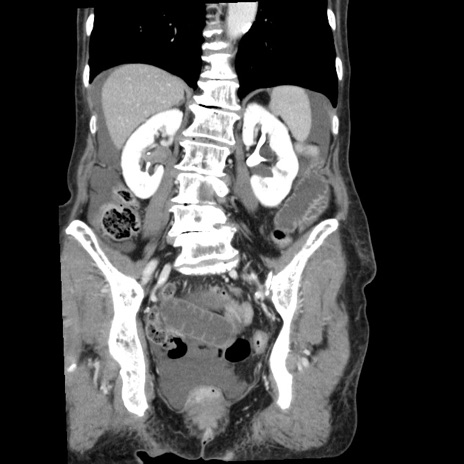

症例1(冠状断像)

【症例】80歳代女性

【主訴】腹痛

【現病歴】8時間前から腹痛あり来院。

【既往歴】糖尿病、脂質異常症、子宮体癌にて子宮全摘術

【身体所見】意識清明・会話良好だが腹痛で苦悶様、全腹部にわたって反跳痛と圧痛あり

【データ】WBC 13600、CRP 0.14、LDH 224、CK 90